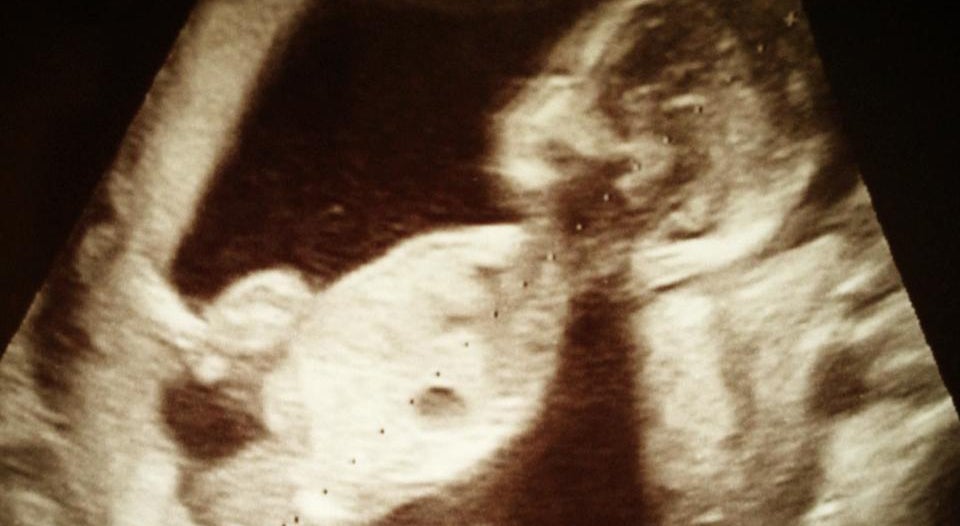

私は、妊娠7ヶ月中期検診にて胎児の心臓異常が発覚し心臓の心室が1つしかない重い障がいと診断されました。